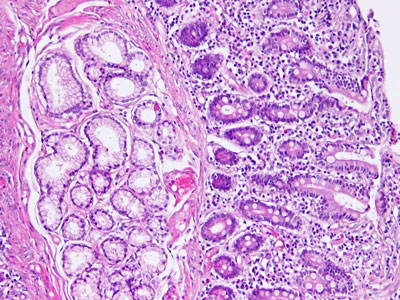

ブルンナー腺(ブルンナーせん、英: Brunner's glands)、あるいはブルンネル腺、十二指腸腺(duodenal glands)は、十二指腸の部分から発見された胆膵括約筋の上に位置する複合環状粘膜下層腺である。ブルンナー腺は粘液に富んだアルカリ分泌物を産生する。この分泌物は次のような役割を持つ。

- Histology image: 11504loa — ボストン大学の組織学学習システム - "Digestive System: Alimentary Canal: pyloro/duodenal junction, duodenum"

- Histology image: 11513loa — ボストン大学の組織学学習システム - "Digestive System: Alimentary Canal: pyloro/duodenal junction"